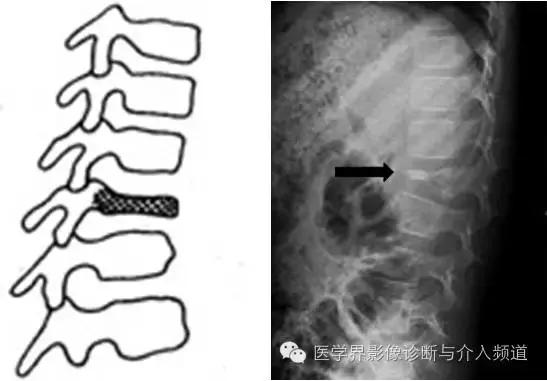

椎体骨软骨病(Calve病),又称扁平椎,是一种少见的骨软骨病。

【定义】Calve病是由于椎体的原发骨化中心发生无菌坏死,继而在脊柱纵向压力作用下,使病椎变扁,骨质致密甚至碎裂。

【X线表现】①好发于下胸椎,少数发生于腰椎,常只累及一个椎体;②椎体呈扁平犹如一枚硬币,其前后径及横径较相邻的椎体为大,骨质致密,边缘光滑;③邻近椎间隙无改变或轻微的增宽;④椎弓根及附件不受侵犯,无椎旁脓疡或软组织肿块阴影;⑤病变愈合后椎体的高度及密度可完全或部分恢复。